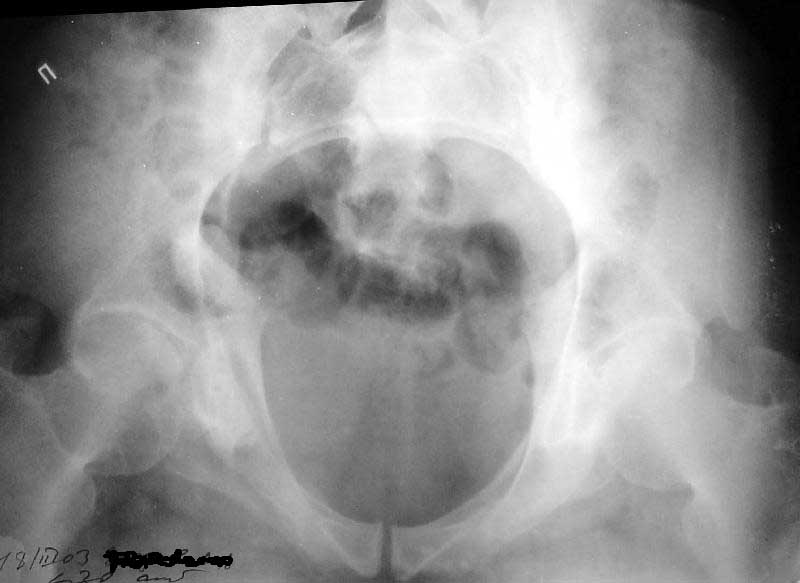

ФасInlet

Больной 64 лет, работник тяжелого физического труда, 29.10.02 на производстве получил удар трубой по переднему отделу таза. 2 месяца постельного режима, с 4 месяцев ходит с тростью. Беспокоят тянущие боли в нижних конечнстях при нагрузке, периодически ночные боли, хромота, постоянно припимает анальгетики. Снимки прилагаются. Виден подвывих в правом крестцово-подвздошном сочленении. Как лучше помочь пациенту? Заранее спасибо.

Based on the CT images you provided, he appears to have a nonunion of the the right ischium, which would explain his symptoms. General principles of treatment of hypertrophic (which this appears to be) nonunions suggest rigid fixation, but I'm not sure what the best approach would be. Could get a lag screw across the fracture through a Kocher-Langenbeck approach or plate osteosynthesis through direct ischial approach, but perhaps Chip, Adam or someone with more pelvic fracture experience could enlighten us all.

I think this is just a pelvic ring disruption that has gone on to a non-union. The arrow is pointing to the inferior ramus non-union, and

the sup ramus is a high "root" fracture, right near the pecten. The sup ramus fracture enters the tab - you could call it an acetabular

fracture - but down here in Dallas we treat these acutely as stable pelvic ring injuries. The fracture in the anterior portion of the

acetabulum is so low it doesn't seem to cause much trouble.

His R sacroiliac joint is opened anteriorly a little bit - the "unreduced posterior lesion" Alex mentioned in his first post. My earlier post about plating, bone grafting, etc., is all wrong.

Речь идёт о коплексном двустороннем повреждении таза с нарушением тазового кольца.

А именно: разрыв илио-сакрального сочленения справа, на этой же стороне трансацетабулярный перелом с незначительным смещением, перелом подвздошной кости слева. Исходя из вышеперечисленного, меня не удивляют двусторонние жалобы пациента. Однако, учитывая представленные снимки ЯМР и времени, прошедшим с момента травмы мне представляется пока преждевременным говорить об образовании ложных суставов. Судя по развиввшейся костной мозоли в области вышеперечисленных очагов, все переломы находяться в стадии консолидации. Вполне возможно, однако, что трансацетабулярный перелом приведёт в дальнейшем к развитию посттравматического артроза ТБ- сустава.